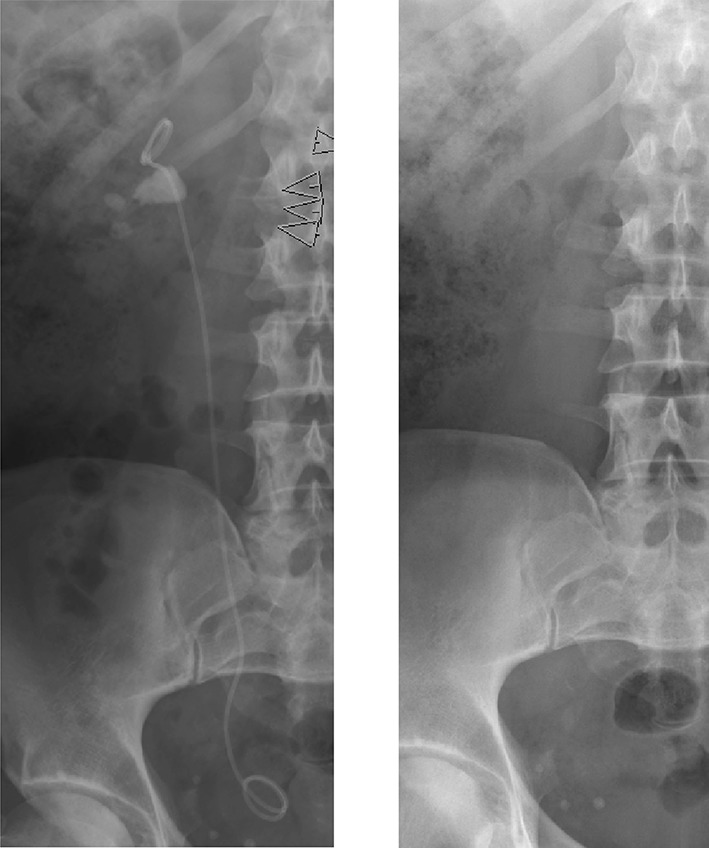

Fig. 3.

Large stone with an internal stent to ovoid steinstrasse. Before SWL (a) and after (b)